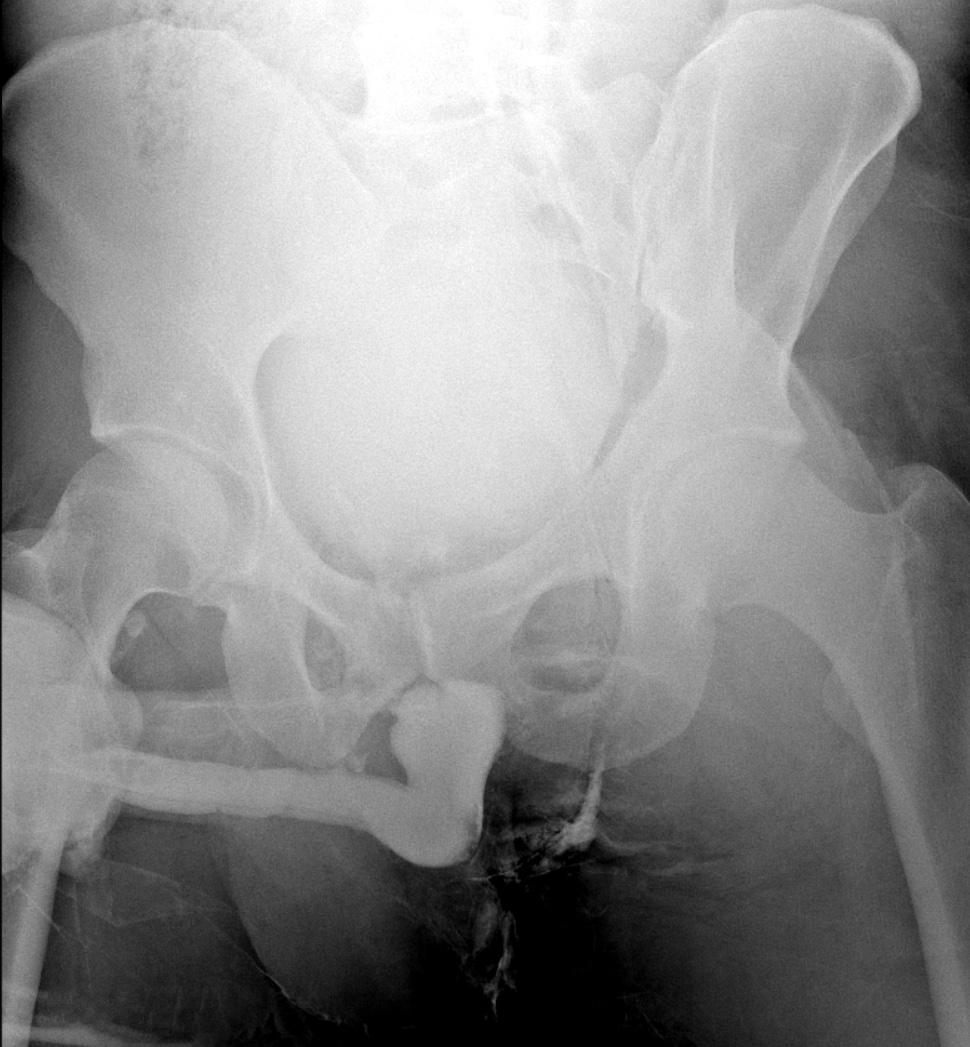

A 35 yo male presents with penile pain, blood at the meatus, inability to void and bruising of his perineum after a surfing injury where he landed on a rock in straddle position. Imaging is done including a retrograde urethrogram shown below. What's the diagnosis? Scroll down for answer.

- How to perform: insert small foley catheter (10F) into tip of penis, inflate balloon slightly so contrast does not leak, inject contrast and take xray to observe if contrast reaches the bladder or if there is blockage or extravasation. CT cystogram can also be done, but is less sensitive for urethral injury.

The case: this patient's retrograde urethrogram shows that the contrast does not enter the bladder suggesting complete blockage or transection. The faint contrast in the bladder is from prior CT cystogram. Urology emergently placed a suprapubic catheter and patient was scheduled for reconstructive surgery later in the week.